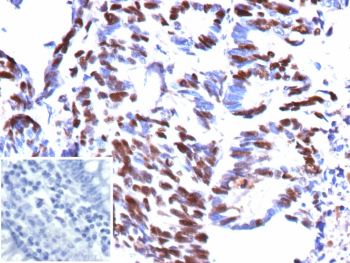

IHC analysis of formalin-fixed, paraffin-embedded human colon tissue using recombinant Minichromosome maintenance protein 5/MCM5 antibody (recombinant mouse monoclonal clone rMCM5/13646). Strong nuclear brown chromogenic staining is observed in proliferating colonic epithelial cells, consistent with nuclear localization of Minichromosome maintenance protein 5, while surrounding non-proliferative cells show reduced staining. Inset: PBS used in place of primary antibody as secondary-only negative control. Heat-induced epitope retrieval was performed by boiling tissue sections in 10mM Tris with 1mM EDTA, pH 9.0, for 45 minutes at 95oC followed by cooling at room temperature for 20 minutes.